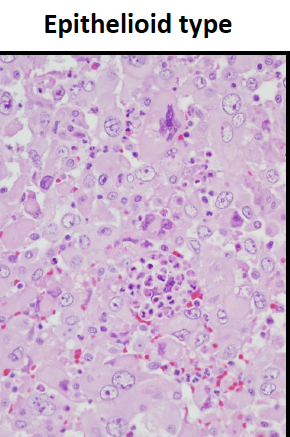

Medullary CA

Histology

Immunochemistry